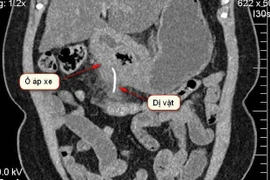

Bệnh viện Thống Nhất, TP HCM vừa phẫu thuật thành công cho người đàn ông bị thủng đại tràng, áp xe gan do nuốt phải xương.

Vô tình nuốt xương cá, chiếc xương nhọn tạo áp xe suýt chút nữa làm thủng dạ dày người phụ nữ.